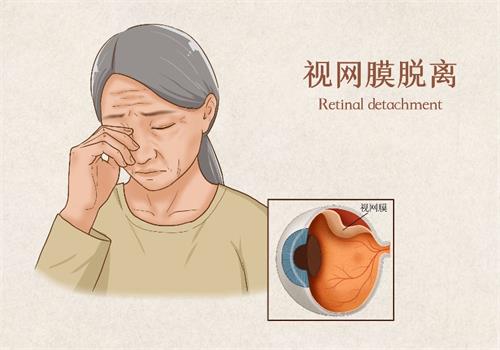

余锦强医师是玻璃体视网膜疾病领域的显要,尤其擅长复杂性视网膜脱离、糖尿病视网膜病变的小创口玻切手术,手术精细度高,视功能重建改善显著。华远锋副高医师则在眼外伤急诊处理方面技术娴熟,能够及时救治眼球破裂伤等急症,更大限度保留患者眼球结构和功能。